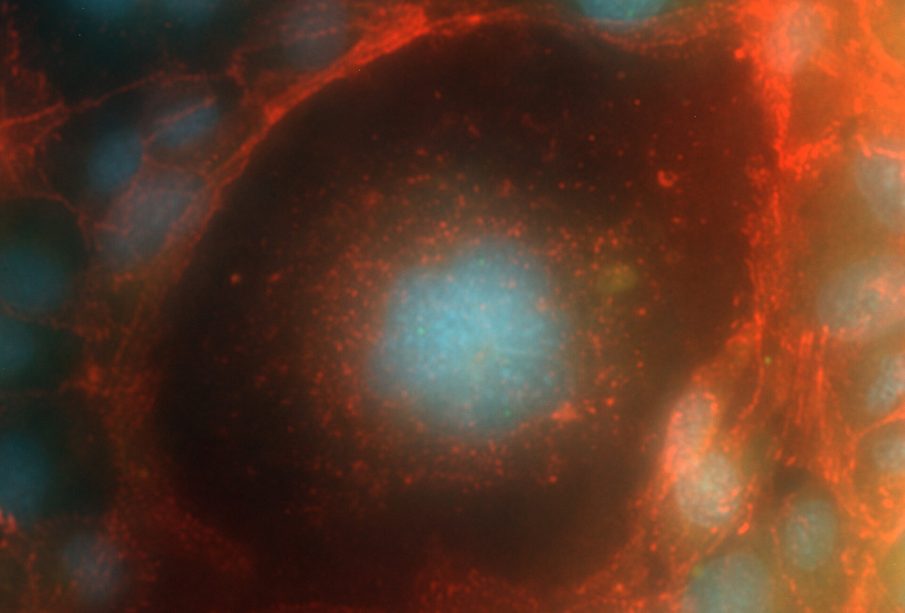

Για τους περίεργους, η εικόνα δείχνει ανθρώπινα τριχοειδή ενδοθηλιακά κύτταρα HMEC-1, κόκκινο: b-catenin, μπλε: πυρήνες, χρησιμοποιώντας μικροσκόπιο Fluorescence Zeiss PALM MicroBeam με μεγέθυνση 63x.